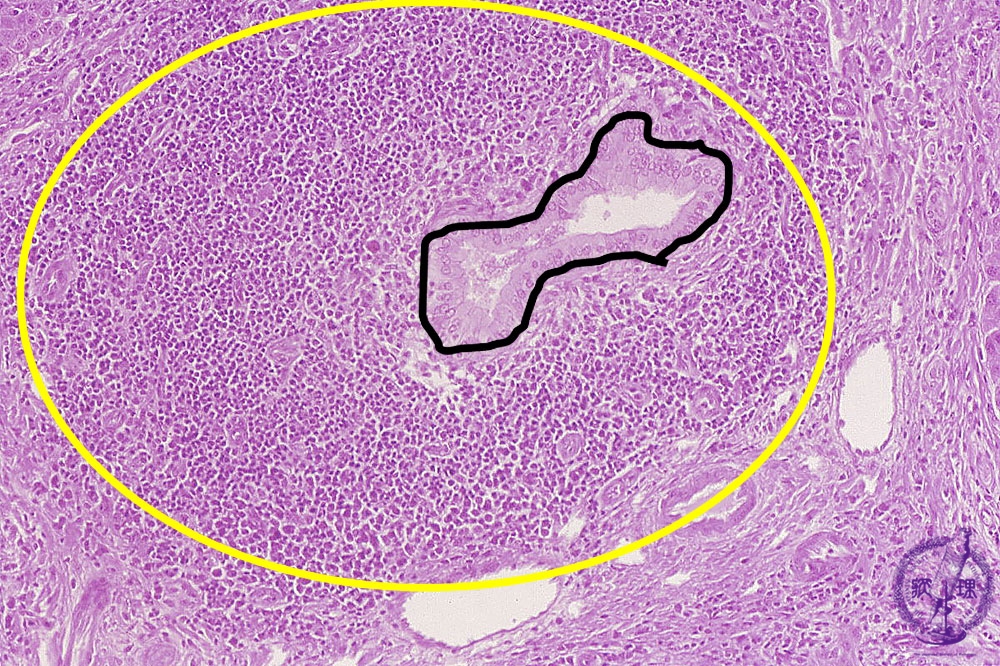

- 肝生検

PBC と PSC は両方とも胆管の損傷を伴います。 PSC は主に肝臓の内外の中・大胆管に損傷を引き起こします。 PBC は、肝臓内の小さな胆管の損傷を特徴としています。